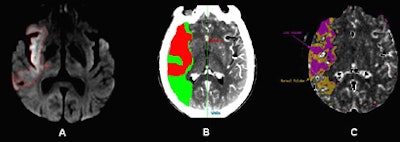

| DWI and CT-CBV images from an 80-year-old patient who presented with left-sided hemiparesis and aphasia 1.5 hours after stroke onset. CT perfusion (CTP) was performed at admission to the emergency department, followed by MR-DWI 40-minutes later. Image A shows the admission DWI lesion. Images B and C show the automatically segmented CT-CBV lesions that optimally correspond to the DWI lesion, using an approximate threshold of 56% reduction in blood volume compared to the contralateral uninvolved side (the fully automated CTP map segmentation was performed using software from two different commercial vendors). All images courtesy of Dr. Shamir Kamalian and Dr. Michael Lev. |

In this heterogeneous group of anterior infarction cases, relative more than absolute CT-CBV thresholds were highly correlated with DWI in the acute determination of infarct core, the authors noted.

"This is likely due large to the difference between gray and white matter in baseline normal CBV values," they wrote. "Despite a very similar r² for relative thresholds of 56% and 66%, the former shows a slope closer to 1, and the latter yielded several visible false-positive regions (red on the maps, but normal in DWI) in 14 patients. Based on our results we suggest the use of a relative threshold of 56% for automatic segmentation of infarction core."